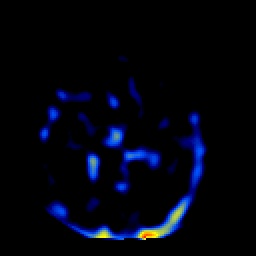

SPECT TL Study #2 -- Slice #28

[Home][Help][Clinical][Tour 1][Tour 2][Tour 3] Slice 28